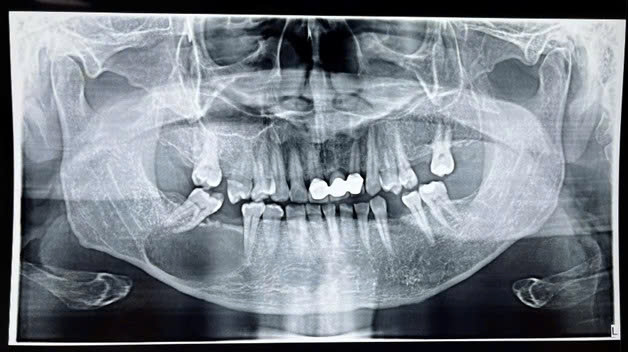

Hình chụp phim X-quang trước mổ và sau mổ của bệnh nhân.

Tuy nhiên, kết quả phim X-quang toàn cảnh (panorama) và CT tại bệnh viện cho thấy hình ảnh hoàn toàn trái ngược: bệnh nhân có tổn thương thấu quang kích thước lớn ở xương hàm dưới bên phải.

Nguyên nhân ban đầu được xác định xuất phát từ chân răng số 46 còn sót lại, đã hư hỏng từ lâu. Nang quanh chóp răng này phát triển lan rộng, không chỉ phá hủy xương hàm mà còn xâm lấn, gây ảnh hưởng trực tiếp và đẩy di lệch ống thần kinh răng dưới – dây thần kinh quan trọng chi phối cảm giác vùng môi dưới và vùng cằm.